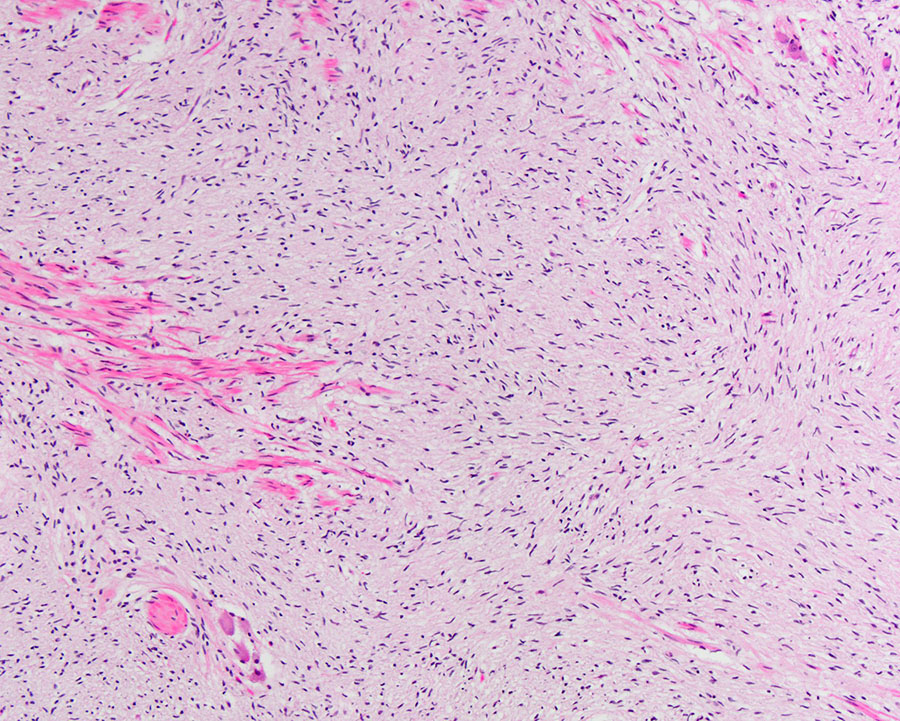

Microscopic examination of the appendix demonstrated a well-circumscribed lesion within the appendiceal wall (Figure 1A). The lesion was predominantly composed of a proliferation of cells with amphophilic to clear cytoplasm and bland spindled to wavy nuclei (Figure 1B). There were also scattered larger cells with abundant eosinophilic cytoplasm, some with granular cytoplasmic pigment, and eccentrically placed round nuclei with vesicular chromatin and prominent nucleoli (Figure 1C). No mitotic figures or cytologic atypia were identified. Immunohistochemical analysis showed the spindled cells and larger cells were highlighted by S-100 protein (Figure 1D), while only the larger cells were positive for synaptophysin (Figure 1E).